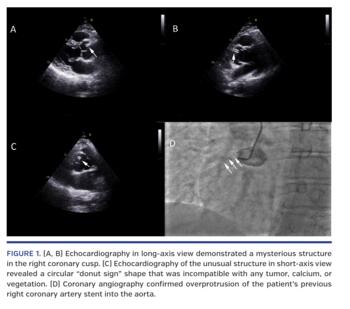

A hypertensive, diabetic man in his 60s with previous history of multivessel stenting presented with class 3 angina despite optimum medical therapy. On transthoracic echocardiography, there was an unusual, non-mobile, echodense, railroad-track like structure measuring 13 x 4 mm in the right coronary cusp (Figures 1A and 1B; Videos 1 and 2) in long-axis view. It appeared to be a circular, donut-like structure (“donut sign”) in the right coronary cusp (Figure 1C; Video 3) in short-axis view. The echocardiographic features of this mysterious structure were not compatible with any tumor, calcium, or vegetation. As the patient had history of coronary intervention in the past, we suspected overhanging stent from the right coronary artery (RCA). Selective coronary angiogram confirmed overprotrusion of his RCA stent into the aorta (Figure 1D; Video 4). This stent overprotrusion barred us from selective engagement of RCA.